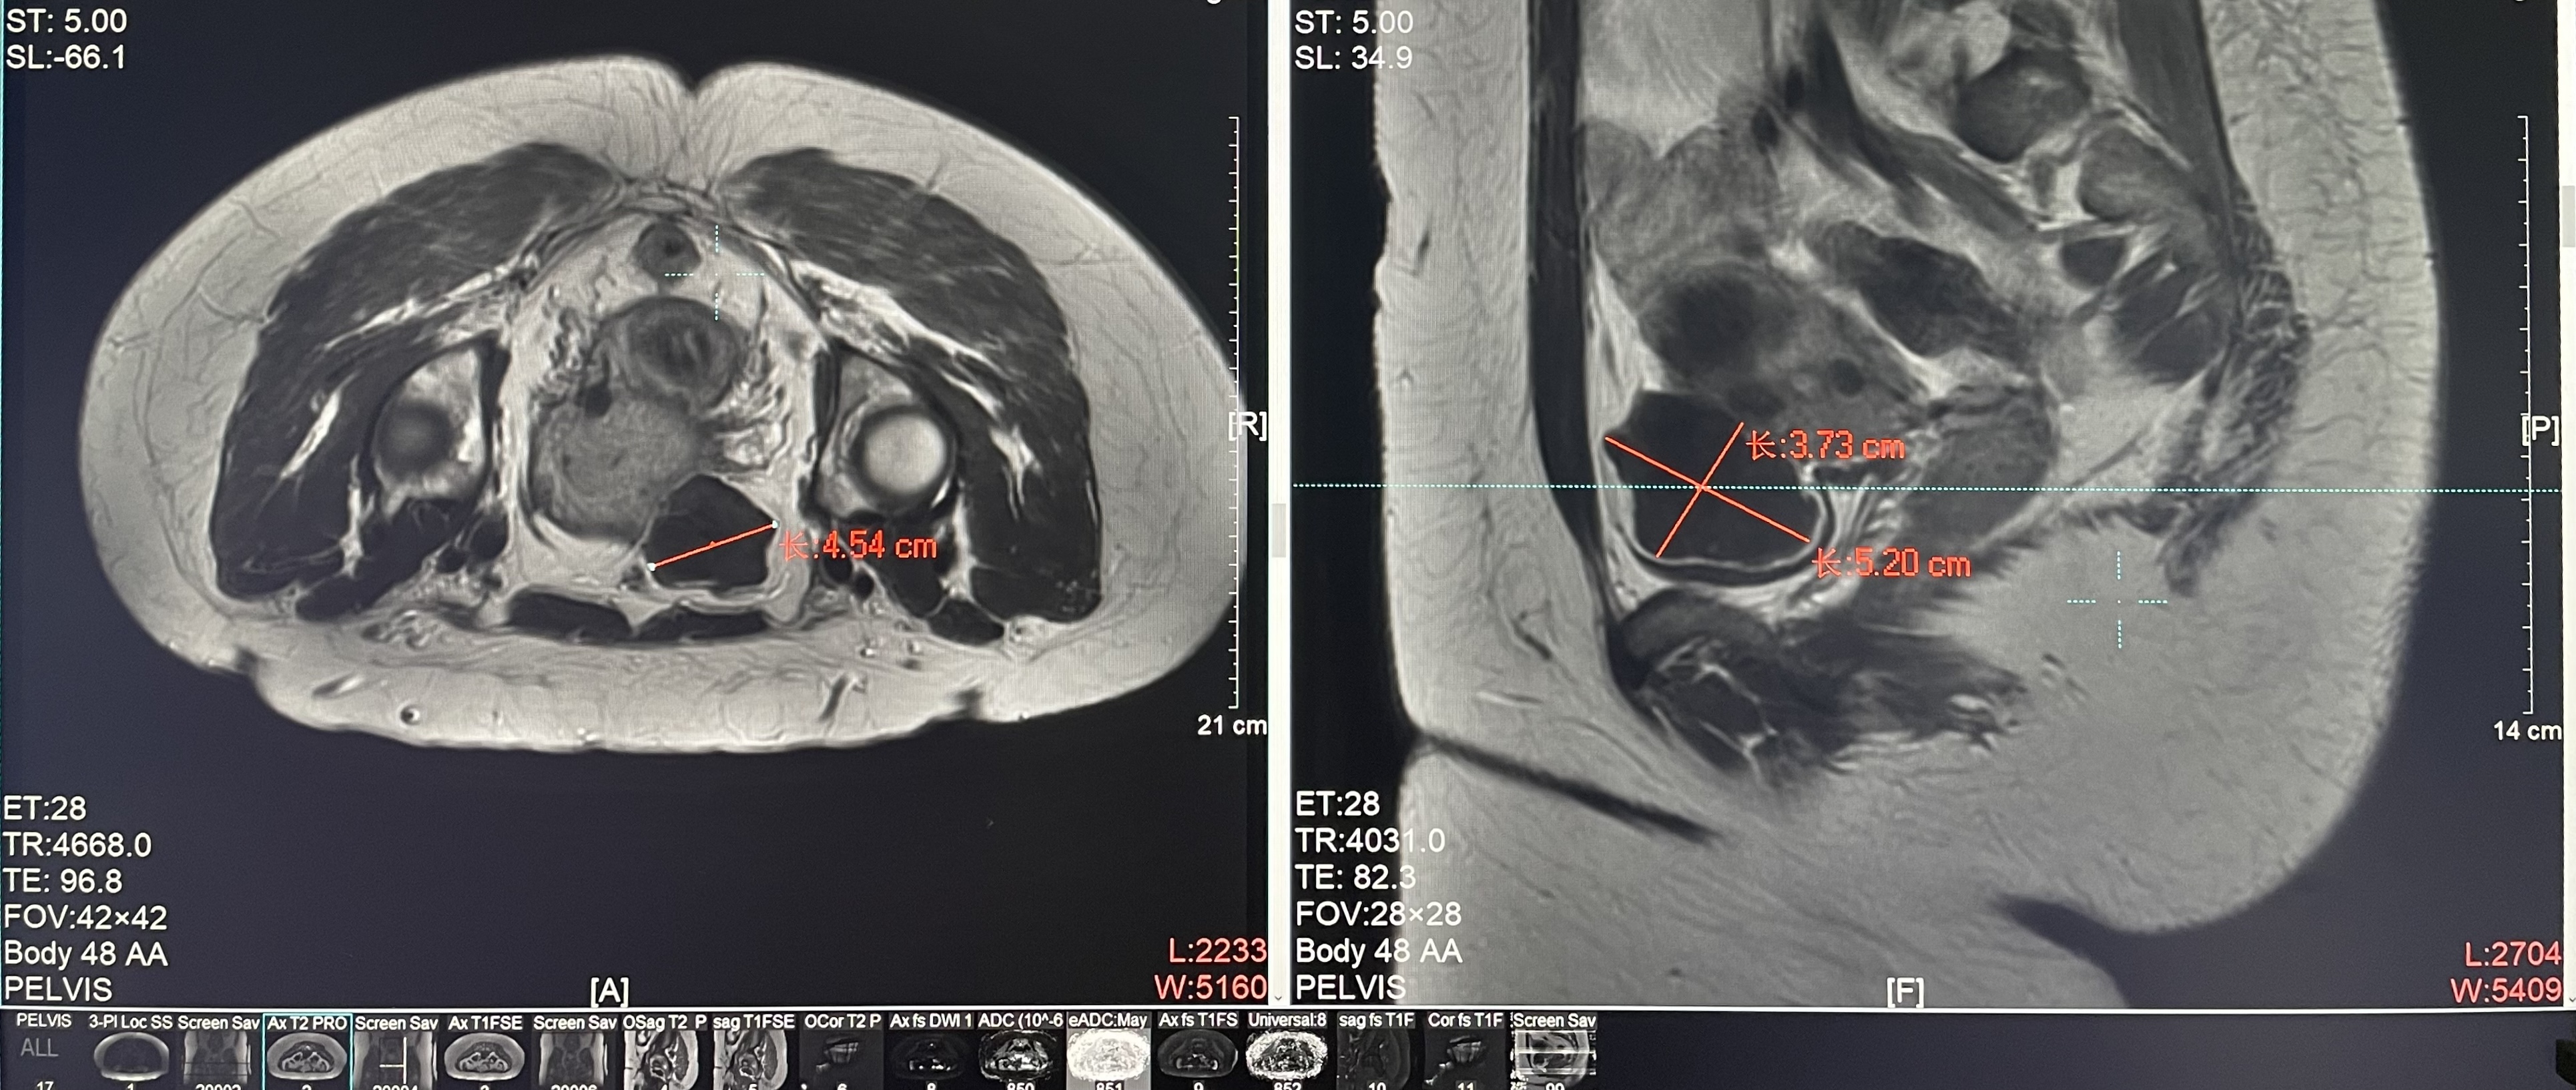

診斷:子宮肌瘤

腫瘤尺寸:約為38*40*42mm

ROT深度:腫瘤的ROT中心距離皮膚62mm

術(shù)后評估:術(shù)后造影增強圖像顯示消融區(qū)域(右側(cè))與腫瘤區(qū)域(左側(cè))重合度較好,且非灌注區(qū)域連續(xù)且一致。

結(jié)論:對該腫瘤具有非常好的消融效果,治療過程中,溫度上升曲線符合預期,每個被治療的靶點240CEM區(qū)域體積較大、外形飽滿、連續(xù)。病灶消融良好,NPV體積比約87.88%。